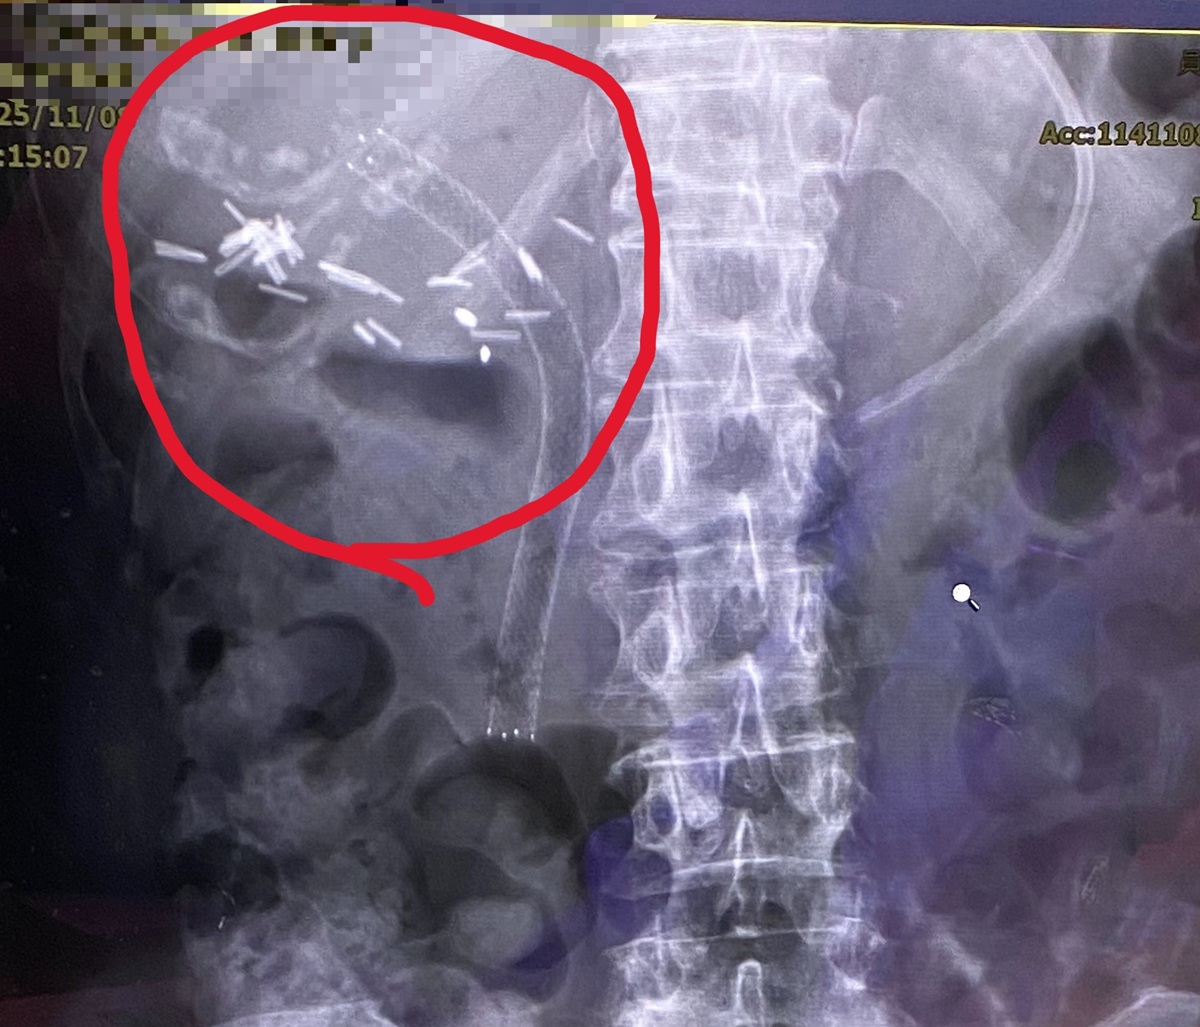

經由逆行性胰膽管鏡檢查發現,原有塑膠支架已完全被膽汁阻塞,使肝內膽管擴張。手術團隊以精準技術使導管通過狹窄處先移除塑膠支架後,再置放金屬膽道支架,讓膽汁得以順利排出。術後X光影像顯示,金屬支架位置良好,膽汁引流恢復正常。患者術後症狀明顯改善,包括腹痛、噁心及黃疸皆逐步消退,肝功能指數亦恢復正常。